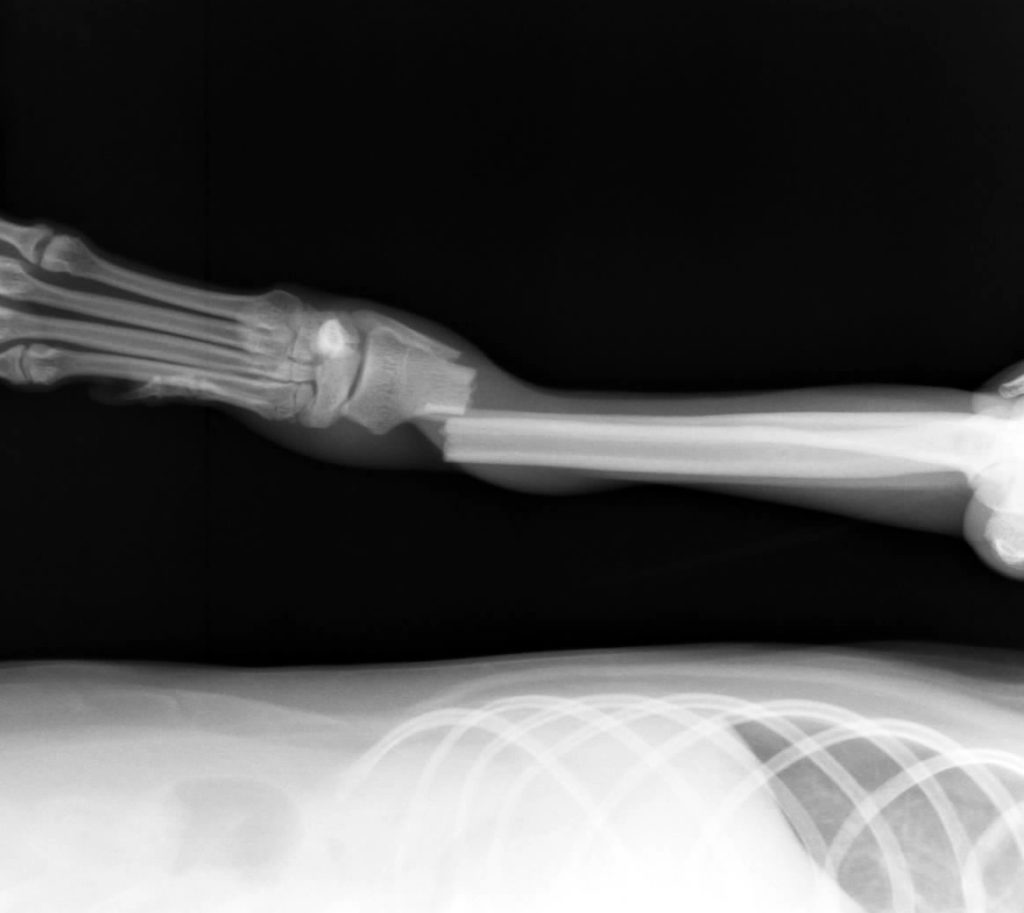

犬の橈尺骨骨折の手術(整形外科) やまと動物病院